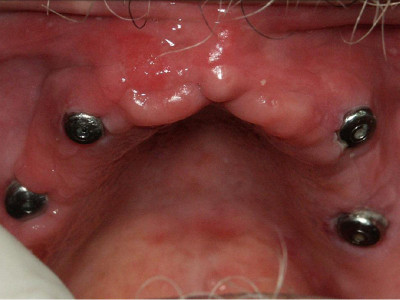

Foto en el cual al paciente se le colocaron cuatro implantes a nivel de maxilar superior